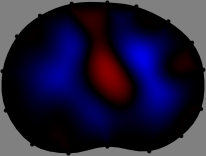

for [23]. This shows that the column vector is like an EEG (electroencephalography) data induced by dipole sources with directions at locations . Given that two dipole sources at distant locations produce mutually independent data, the correlation between and decreases with the distance between and . Fig. 2 shows a few images of the correlation as a function of for four different positions . The correlation decreases rapidly as the distance increases. In the green regions where the correlation is almost zero, is nearly orthogonal to .

Fig. 2 shows that if and are far from each other, the corresponding columns of the sensitivity matrix are nearly orthogonal. This somewhat orthogonal structure of the sensitivity matrix motivates an algebraic formula that directly computes the local ensemble average of conductivity changes at each point using the inner product between changes in the data and a scaled sensitivity vector at that point: